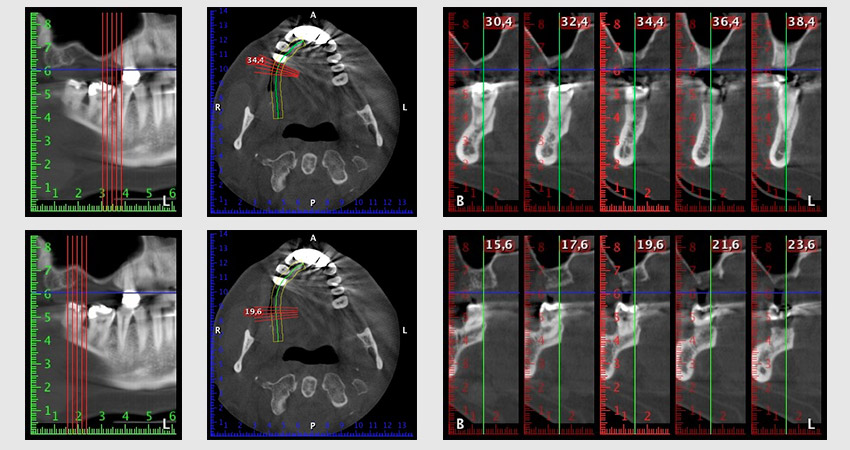

Al fine di pianificare e minimizzare i rischi, circa sei mesi dopo l'estrazione dei denti 16 e 14 viene effettuata una tomografia digitale volumetrica (DVT, Planmeca), la quale conferma chiaramente la mancata rigenerazione ossea nel volume desiderato (da fig. 2 a 7).